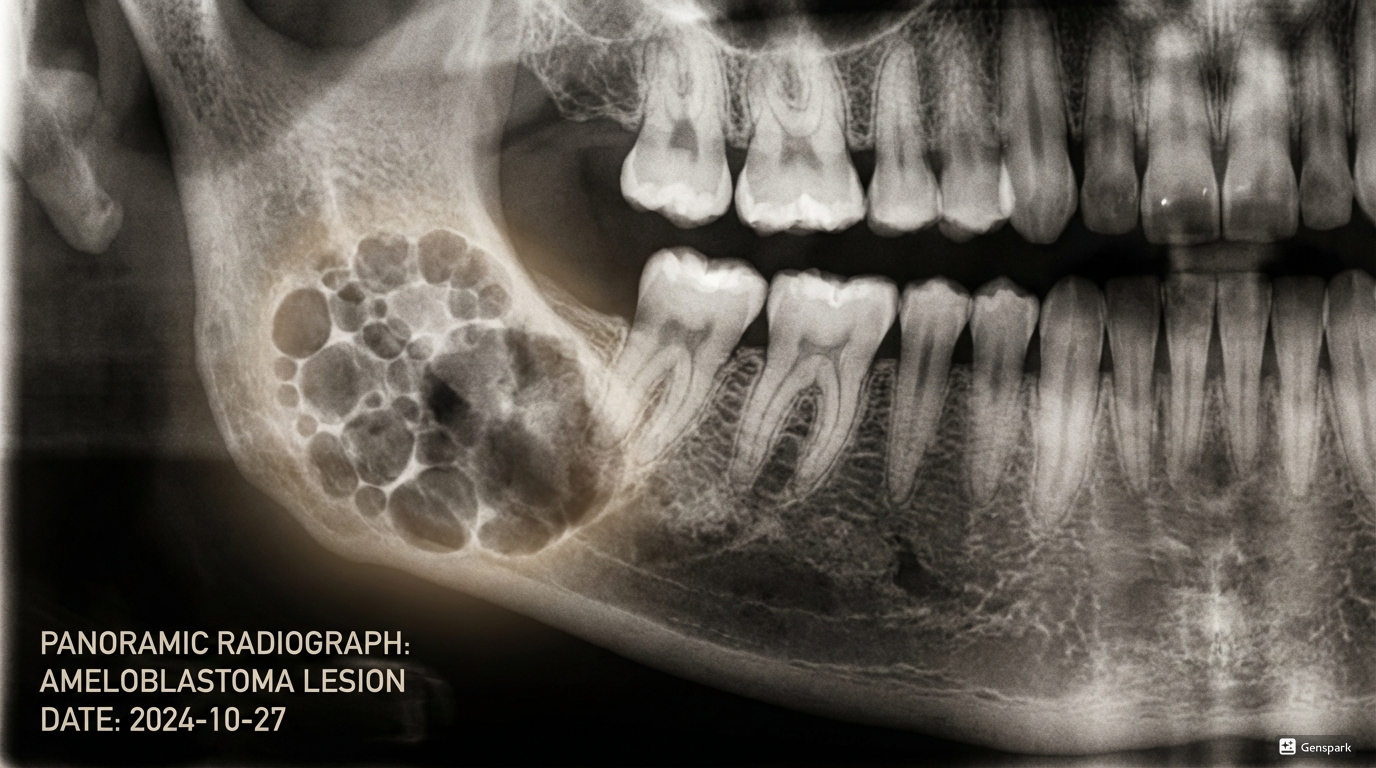

Jaw Cysts & Tumours

Expert surgical care for jaw cysts and tumours, with a strong emphasis on precision, safety, and comprehensive treatment planning.